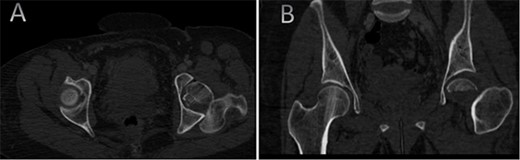

A medically free 42-year female presented to our institute as a life-saving case from a different hospital as she was a victim of unrestrained road traffic accident 2 days prior to presentation. Upon assessment in the emergency department (ER), she was conscious and oriented, and was found to have bilateral lung contusion, and multiple fractures of ribs. She also had a left sided vertical femoral head fracture dislocation comprising around 40% of the femoral head (Fig. 1). Closed reduction under conscious sedation was done in the ER, which was successful based on post-reduction imaging studies (Fig. 2). Her chest injuries were treated with chest tube and observation for 10 days. During that time, discussion was made with the patient regarding her situation and conservative management was chosen by way of bed rest and continuation of skeletal traction for 4 weeks with serial radiographs in the hospital on a weekly basis after clearance of her chest injuries. Skeletal traction was discontinued and she was advised to continue bed to wheelchair mobilization for an additional 2 weeks. After 6-weeks from the injury, a Computed Tomography (CT) was done to the patient and revealed signs of fracture healing (Fig. 3). At 3-years after the injury, she was found to have full painless range of motion of the affected hip and has resumed her activity of daily living without any complaints and the images showed a symmetrical joint space of the hips (Fig. 4).

CT scan of the chest, abdomen, and pelvis showing axial (A) and coronal (B) cuts of a left sided Pipkin I fracture comprising large surface of the femoral head with posterior hip dislocation.

CT scan of the pelvis showing axial (A) and coronal (B) cuts at 6-week post-injury showing signs of healing of the left fractured femoral head with a concentric hip joint.